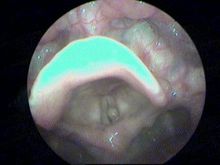

主要的臨床症狀為聲音嘶啞,典型的聲帶囊腫診斷較為簡單,電子喉鏡下聲帶表面或邊緣可見黃白色隆起,透過聲帶的黏膜可見其內黃白色的囊液,而對於較深在的聲帶囊腫及巨大聲帶囊腫,電子喉鏡下診斷有一定的難度,巨大的聲帶囊腫有時易誤診為聲帶水腫及息肉樣變。

對於不能確診的病例,頻閃喉鏡有助於診斷,聲帶振幅變小,黏膜波減弱、不連續或消失提示為聲帶囊腫。聲帶囊腫的手術,也經歷了間接喉鏡、直達喉鏡、支撐喉鏡喉顯微手術幾個階段。